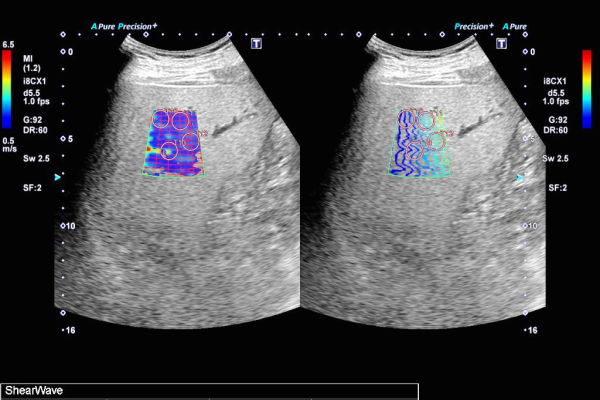

腹部超音波検査では上記に記載の臓器に病変がないかを調べる以外にも、肝臓の硬さを計測して数値化する肝エラストグラフィという検査や、肝臓の腫瘤に対して造影剤を用い、腫瘤が悪性腫瘍(肝細胞癌や転移性肝癌など)かどうかを調べる検査も行っています。また、超音波減衰法を用いて肝臓の脂肪量を数値化し、脂肪肝の程度を定量的に評価することができる装置を導入しています。

肝エラストグラフィ